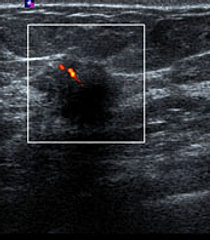

Breast Ultrasound: Benign Vs. Malignant Lesions

Breast ultrasound not only helps in differentiating cystic from solid lesions, but also plays an important role in characterizing solid nodules. ... View Doc